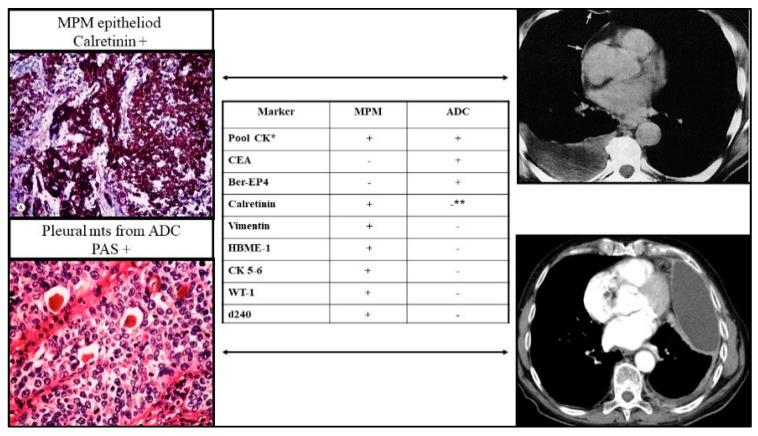

MPM has a uniquely poor somatic mutational landscape, mainly driven by environmental selective pressure. This feature has dramatically limited the development of effective treatment. However, genomic events are known to be associated with MPM progression, and specific genetic signatures emerge from the exceptional crosstalk between neoplastic cells and matrix components, among which one main area of focus is hypoxia. Here we discuss the novel therapeutic strategies focused on the exploitation of MPM genetic asset and its interconnection with the surrounding hypoxic microenvironment as well as transcript products and microvesicles representing both an insight into the pathogenesis and promising actionable targets.

恶性胸膜间皮瘤具有独特的、较差的体细胞突变格局,主要由环境选择压力驱动。这一特征极大地限制了有效治疗方法的开发。然而,已知基因组事件与恶性胸膜间皮瘤的进展相关,并且特定的基因特征源自肿瘤细胞与基质成分之间特殊的相互作用,其中一个主要关注领域是缺氧。在此,我们讨论了新的治疗策略,这些策略专注于利用恶性胸膜间皮瘤的遗传特性及其与周围缺氧微环境的相互联系,以及转录产物和微泡,它们既有助于深入了解发病机制,也是有前景的可操作靶点。